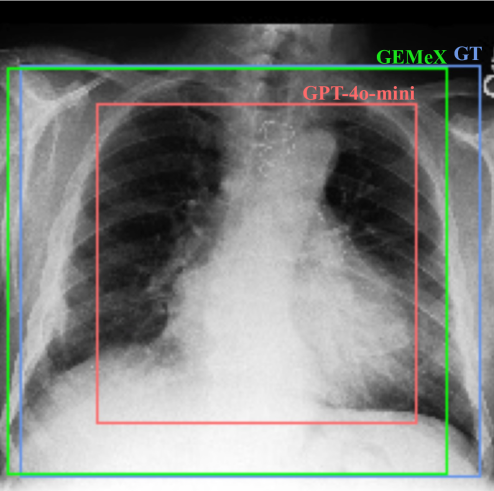

• Powerful LVLMs like GPT-4o-mini often rely on shortcut reasoning instead of true multimodal reasoning. Specifically, while they can sometimes answer questions to a certain extent, they often fail to accurately visual grounding. This indicates that these models tend to solve Med-VQA tasks using shortcut knowledge, such as retrieving information from their pre-training memory, rather than engaging in genuine multimodal reasoning. However, multimodal reasoning is central to the explainability of Med-VQA systems.

• Through the proposed simple question-type-aware instruction tuning, the model achieves a significant performance improvement, approximately 13.5% (i.e., avg. AR-score) compared to LLaVA-Med-v1. More importantly, it surpasses GPT-4o-mini on most metrics, demonstrating the reliability of the training set. However, there still remains a significant gap towards practical usage, highlighting the challenges of the proposed GEMeX.